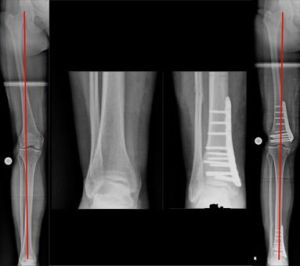

Beispiel einer aufklappenden Osteotomie, kniegelenksnah, am Schienbein bei O-Beinfehlstellung. Die MA wurde zentriert, da noch keine Schädigung des Gelenkes vorlag (Bild 2).

Individualisierte Vorgehensweise beim O-Bein (Bild 4). Infolge einer Verletzung der kniegelenksnahen, innenseitigen Wachstumsfuge resultierte dort eine diskrete Beinverkürzung mit O-Beinfehlstellung. Durch das aufklappende Verfahren wurden sowohl Beinlänge wie –achse ausgeglichen.